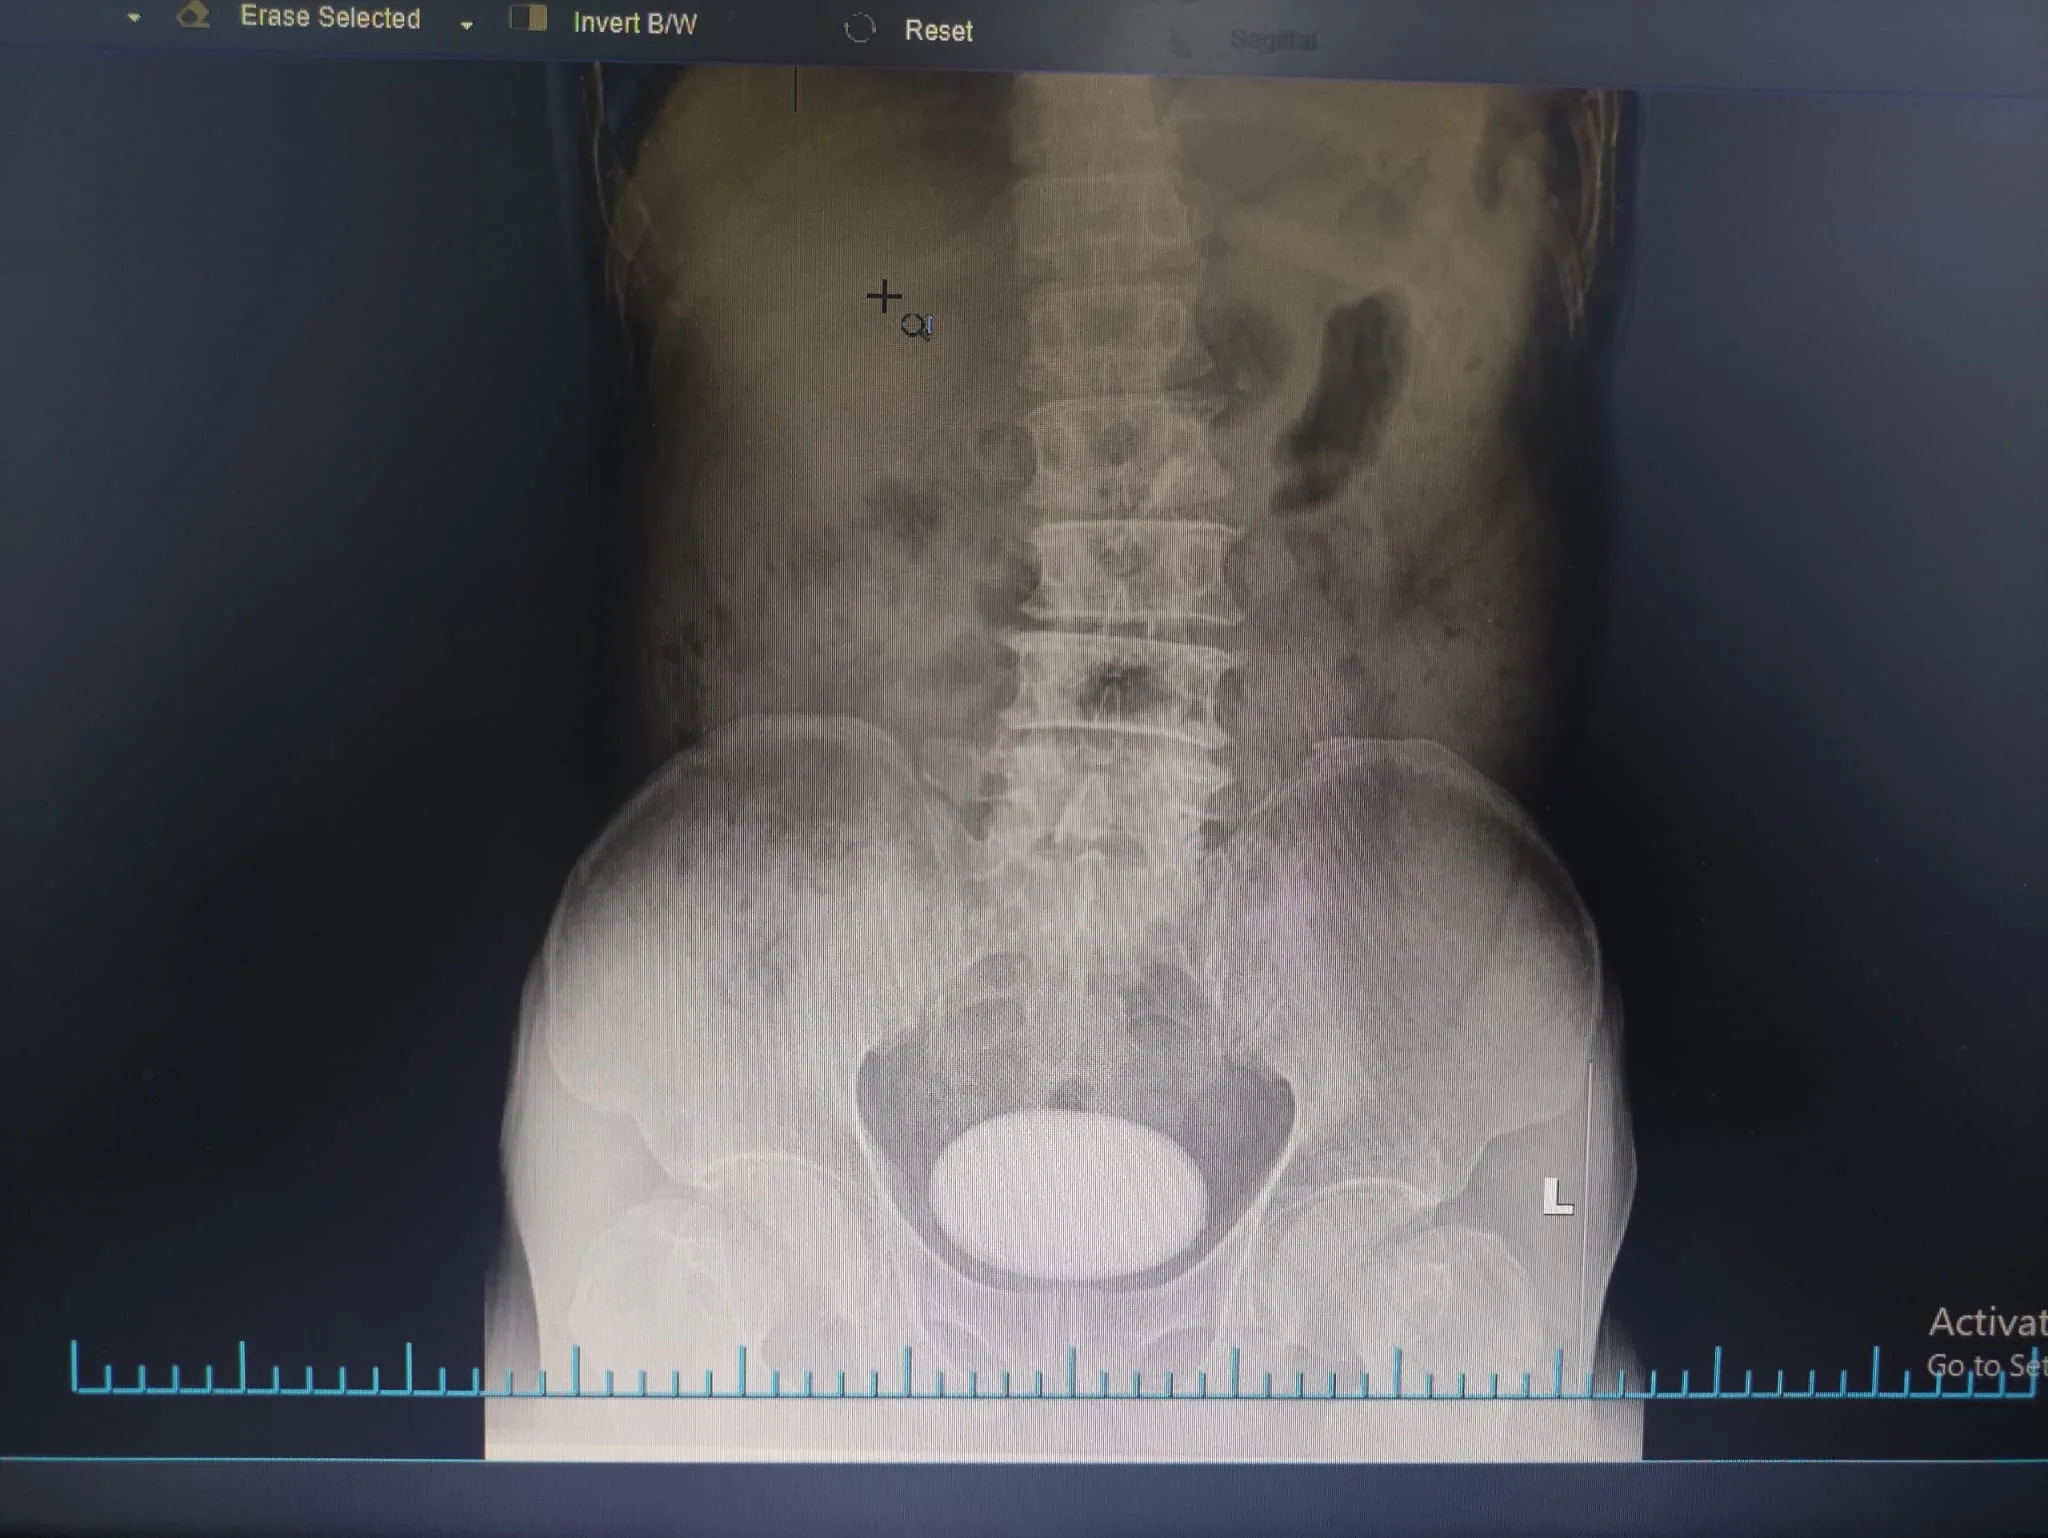

Bệnh nhân nam 57 tuổi nhiều tháng nay đau hạ vị, tiểu buốt, tiểu rắt kéo dài, tự ý dùng thuốc nhưng không đỡ. Người bệnh ngày càng đau tăng lên kèm tiểu buốt rắt rất nhiều, bệnh nhân vào Bệnh viện đa khoa quốc tế Hải Phòng thăm khám. Sau khi thăm khám và làm các xét nghiệm cận lâm sàng cần thiết, bác sĩ phát hiện người bệnh có sỏi bàng quang lớn, kích thước 6-8cm. Bàng quang bị viêm nặng, niêm mạc phù nề và thành bàng quang dày lên, niệu quản và bể thận cũng đã bắt đầu có biểu hiện bị ứ đọng nước tiểu lâu ngày và bị giãn.

Bệnh nhân được chỉ định phẫu thuật để lấy sỏi bàng quang. Thông thường nếu viên sỏi bàng quang có kích thước dưới 3 hoặc 4cm thì các bác sĩ sẽ dùng kỹ thuật tán sỏi nội soi bằng laser, viên sỏi sẽ được tán nhỏ ra và các mảnh vụn sẽ được lấy ra qua đường niệu đạo, bệnh nhân không có vết mổ và sau phẫu thuật hầu như không đau và phục hồi nhanh chóng. Tuy nhiên ở bệnh nhân này sỏi bàng quang có kích thước “khổng lồ”, quá lớn nên không còn chỉ định tán sỏi và bắt buộc phải phẫu thuật, mở rộng bàng quang để lấy toàn bộ viên sỏi ra ngoài. Viên sỏi được lấy ra có kích thước 10x8cm, nặng gần 400g, quá trình phẫu thuật gặp khó khăn do thành bàng quang viêm rất dày, niêm mạc viêm phù nề dễ chảy máu do sỏi quá lớn và nằm lâu ngày trong lòng bàng quang. Tuy nhiên với tay nghề dày dặn kinh nghiệm và trình độ chuyên môn vững chắc, đội ngũ bác sĩ Khoa Ngoại thận tiết niệu và nam học của Bệnh viện đã thực hiện thành công. Sau mổ, người bệnh sức khỏe phục hồi, vết mổ khô liền tốt.